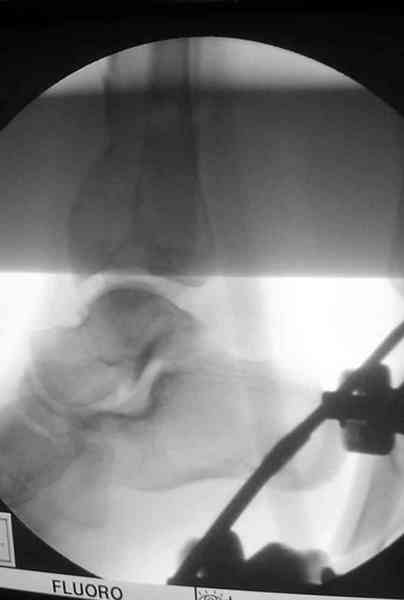

Добавлены КТ снимки. Прошу прощения за качество.

С уважением, Коваленко А.Н.